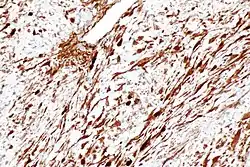

Podstawą rozpoznania guza desmoidalnego jest badanie histopatologiczne materiału uzyskanego drogą biopsji. W badaniu mikroskopowym rozpoznaje się ubogokomórkowy rozrost fibroblastów naciekających sąsiednie tkanki[40].

W badaniu immunohistochemicznym wykrywa się ekspresję wimentyny, SMA (smooth muscle actin), MSA (muscle specific actin) oraz β-kateniny[22][13]. W badaniach genetycznych stwierdza się trisomię chromosomu 8 i 20, a także delecję regionu 5q21-q32[53][13].

Guz różnicuje się przede wszystkim z włókniakomięsakiem, którego od guza desmoidalnego odróżnia atypia komórek wrzecionowatych, większa komórkowość oraz indeks mitotyczny, atypowe komórki i włókna kolagenowe ułożone w wyraźne pęczki, a zrąb jest wyraźnie uboższy[54].